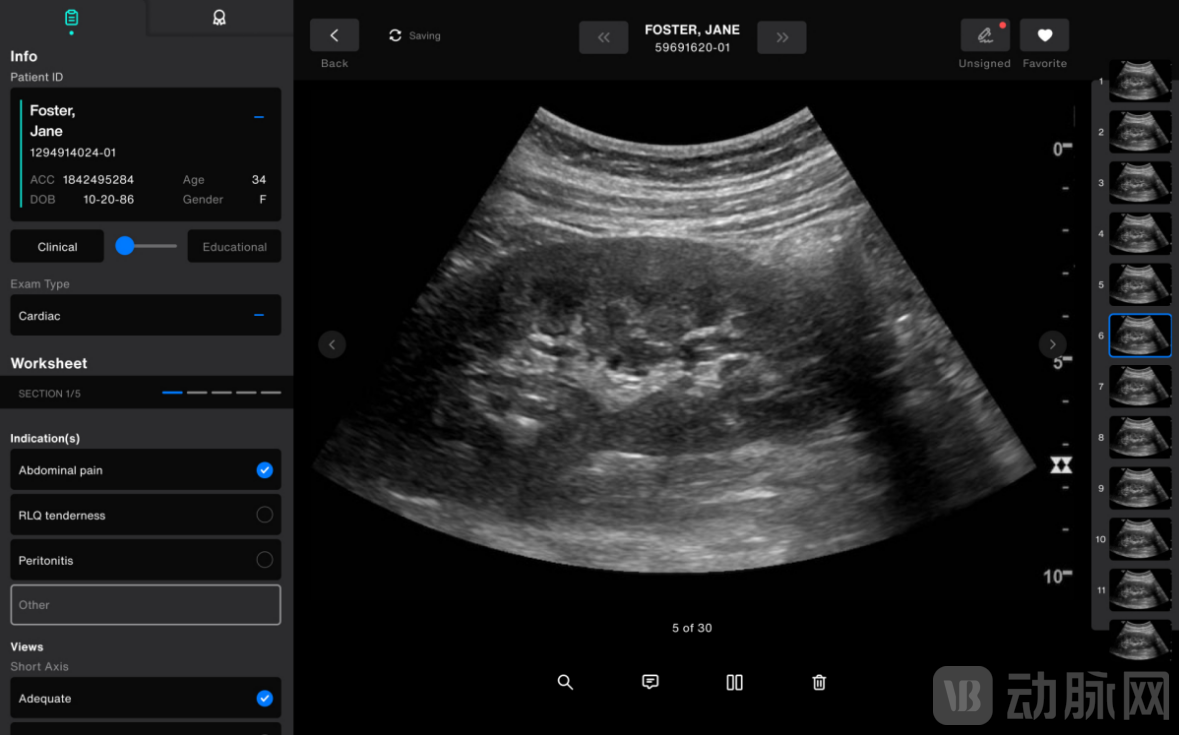

为了优化超声工作流程,Exo推出了一款专为整个医疗系统设计的智能、直观的即时医疗超声工作流解决方案Exo Work,可在急诊或者诊所等应用场景无缝衔接工作。

据了解,Exo Work能够在60秒内完成病例筛查、归档和计费,解决了长达数十年的工作流程问题。

且该软件几乎适用于所有的床旁超声设备,并可安全地到医院使用的EMR和PACS系统中,以容纳成像和通信,连接的便利性最终使互动操作成为现实。

更重要的是,Exo Work的远程质量保证可以允许患者通过远程医疗进行超声波扫描,患者可以在家中使用探头,并由经验丰富的丰富的医护人员远程引导操作。